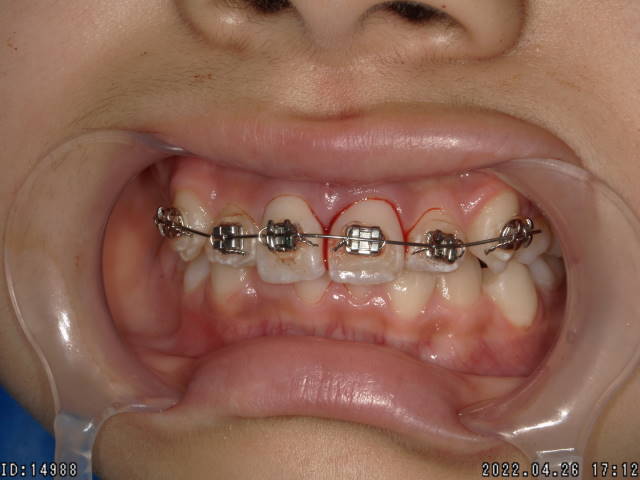

症例1

左上の前歯が不完全脱臼を起こして歯の位置が変位してしまいました。

歯の位置を従来の位置に整復して、4週間程度固定します。